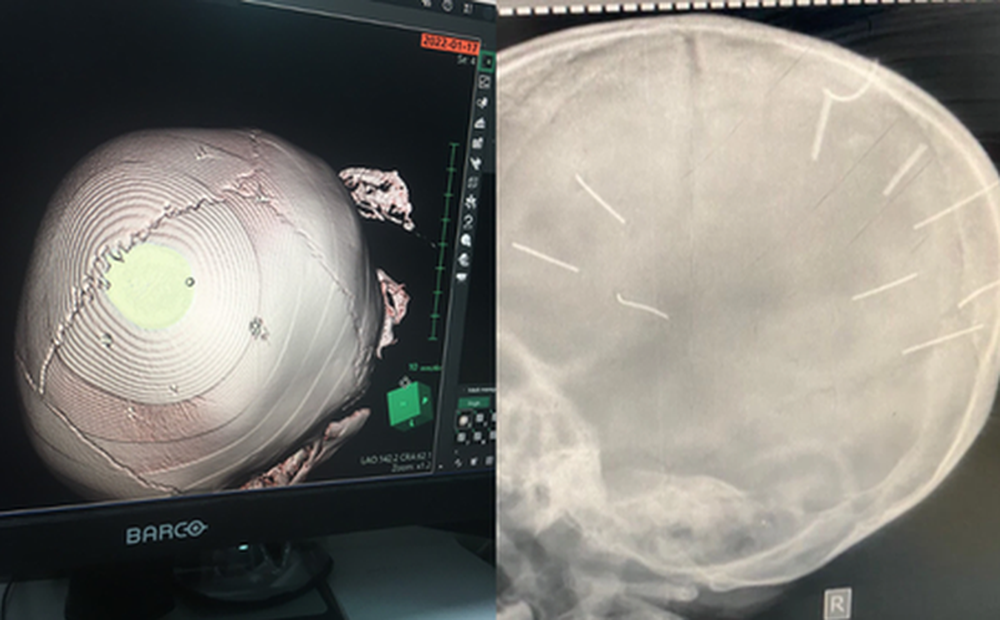

Hình ảnh đinh trong đầu bé gái.

Các bác sĩ khoa Cấp cứu, Bệnh viện Đa khoa huyện Thạch Thất sau khi tiếp nhận bệnh nhân đã tiến hành đặt ống, chụp phim làm chẩn đoán thấy trên phim X-quang có hình ảnh cản quang trên hộp sọ bệnh nhi.

Sau khi bệnh nhi được chuyển đến Bệnh viện Đa khoa Xanh Pôn, đơn vị này đã tiến hành chụp cắt lớp, dựng hình nhận thấy có những hình ảnh giống như đinh gỗ ở sọ và tổ chức não.